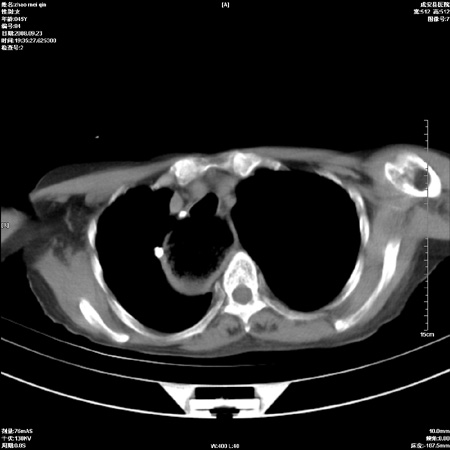

标题: CT15861:女 60 外伤后1小时 胸疼 [打印本页]

标题: CT15861:女 60 外伤后1小时 胸疼

外伤后1小时 胸疼 是外伤后引起的吗?

食道扩张明显下端逐渐变窄,倒像贲门失迟缓

食道ca术后胸腔胃,右肺挫伤?

食道扩张明显下端逐渐变窄,大量食物存留,象贲门失迟缓症。